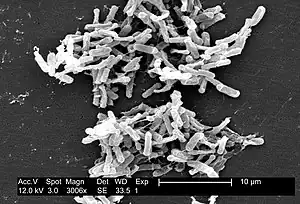

| Electron micrograph of the bacterium | |

Clostridioides difficile (syn. Clostridium difficile) is a bacterium known for causing serious diarrheal infections, and may also cause colon cancer.[4][5] It is known also as C. difficile, or C. diff (/siː dɪf/), and is a Gram-positive species of spore-forming bacteria.[6] Clostridioides spp. are anaerobic, motile bacteria, ubiquitous in nature and especially prevalent in soil. Its vegetative cells are rod-shaped, pleomorphic, and occur in pairs or short chains. Under the microscope, they appear as long, irregular (often drumstick- or spindle-shaped) cells with a bulge at their terminal ends (forms subterminal spores). Under Gram staining, C. difficile cells are Gram-positive and show optimum growth on blood agar at human body temperatures in the absence of oxygen. C. difficile is catalase- and superoxide dismutase-negative, and produces up to three types of toxins: enterotoxin A, cytotoxin B and Clostridioides difficile transferase.[7] Under stress conditions, the bacteria produce spores that are able to tolerate extreme conditions that the active bacteria cannot tolerate.[8]